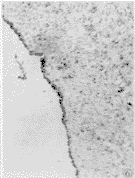

2.1.1 胎盘 胎盘组织内iNOS免疫组化染色显示,正常妊娠组大部分胎盘绒毛合体滋养层细胞不着色,或仅有浅淡着色,残留的细胞滋养层细胞有着色;妊高征者的绒毛合体滋养层细胞较多呈棕黄着色。正常及妊高征胎盘绒毛间质内可见散在的深棕黄色着色的Hofbauer细胞(图1、2)。正常妊娠组胎盘的绒毛干大血管及绒毛小血管平滑肌细胞多着色,内皮细胞扁平,着色少;而妊高征组胎盘的一些绒毛干大血管及绒毛小血管平滑肌细胞着色明显减弱或无,内皮细胞着色增强(图3、4)。

图3 免疫组化: 正常妊娠胎盘,绒毛干血管平滑肌细胞着色明显,内皮细胞几乎无着色。ABC 法 ×100

Figure 3 Immunohistochemistry: Normotensive placenta ,the iNOS staining is stronger in vascular smooth muscle cells of sterm villi and there is very weakly iNOS staining in endothelial cells . ABC ×100

图4 免疫组化:妊高征胎盘,绒毛干血管平滑肌细胞无着色,内皮细胞明显着色。ABC 法 ×100

Figure 4 Immunohistochemistry: Preeclampsia placenta, the iNOS staining is stronger in endothelial cells and no staning in vascular smooth muscle cells of sterm villi. ABC ×100

2.1.2 脐带 正常妊娠组脐动脉、脐静脉平滑肌细胞多有着色,内皮细胞扁平,着色较少;而妊高征组脐静脉或部分脐动脉内皮细胞着色增强(图5、6)。

图5 免疫组化: 正常妊娠脐静脉,内皮细胞iNOS着色少。ABC法 × 100

Figure 5 Immunohistochemistry: Normotensive umbilical vein, iNOS staining in endothelial cells is weak. ABC ×100

图6 免疫组化:妊高征脐静脉,内皮细胞着色明显增强。ABC法 ×100

Figure 6 Immunohistochemistry: Preeclampsia umbilical vein, there is stronger iNOS staining in endothelial cells. ABC×100